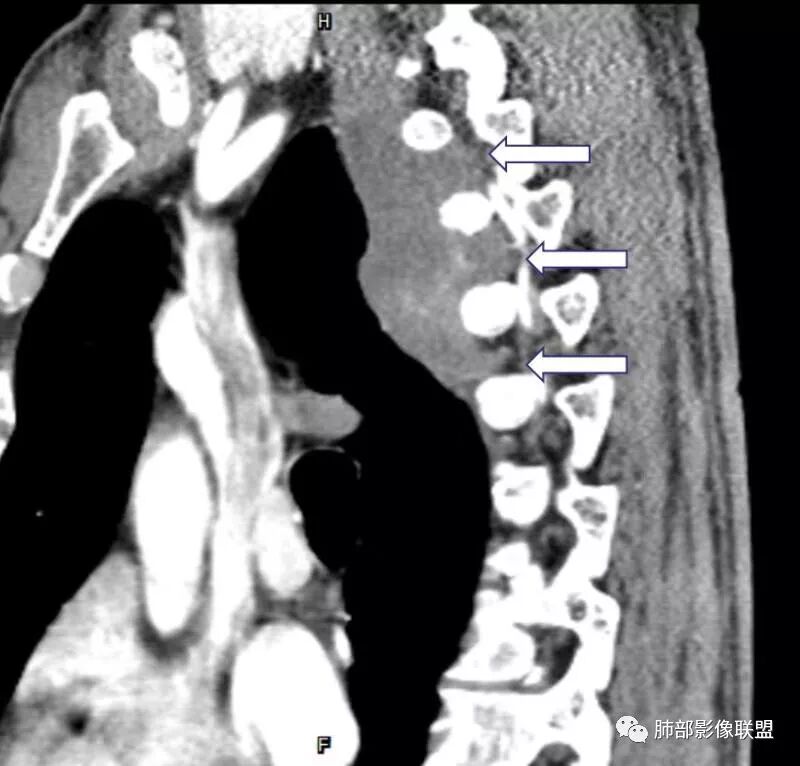

这个病例定位肺外没问题,病灶呈宽基底,见明显的胸膜掀起征,定位胸膜或右后纵隔来源,而且肿块提示肋间动脉穿行,脏层胸膜来源可能性不大(脏层胸膜由肺动脉及支气管动脉供血),那就是壁层胸膜跟纵隔来源,但是图像上有2个层面是胸膜外间隙有受压推移,所以壁层胸膜来源也不考虑;病灶是渐进性强化,常见的就是间叶来源含有梭形细胞的软组织肿瘤跟后纵隔常见的神经源性肿瘤鉴别,那如何在后纵隔的大山里拨开云雾找到我们想要的答案呢?那小编在这里先理出几个问题:

问:这个病例病灶确实邻近椎间孔生长,除了神经源性肿瘤会向椎间孔方向生长,还有什么肿瘤会有这种行为?这个病灶整体形态呈扁平不规则,周围骨质未见破坏,就一定是良性吗?    答:这个病灶明显嵌入式生长,往往提示病灶柔软或有侵袭性,而神经鞘瘤往往有包膜,有张力,典型的形态往往呈类圆形、“逗点形”或“哑铃型”横向延入某一椎间孔内;神经节细胞瘤虽然可以比较柔软,但是具有大量粘液基质,动静脉期强化不明显,延迟强化轻度增强,加之没有钙化,故符合点不多;此外比较柔软的肿瘤如淋巴瘤,但是周围没有肿大淋巴结不太考虑;本例形态不规则的实性肿块,没有明显骨质破坏,倾向具有侵袭性的间叶来源的肿瘤。

答:神经源性肿瘤的解剖位置及形态很重要—沿神经干方向生长走行。后纵膈内神经鞘瘤最常见的是神经根出入椎间孔处,并可沿着肋间神经方向分布,所以后纵膈神经鞘瘤通常横径大,上下径小,这个病例明显上下径长,所以不符合神经鞘瘤;神经节细胞瘤可沿着椎旁上下方向分布(参见上图黄色梭形的神经节),所以表现为上下径长,虽然生长方式符合,但是节细胞瘤以粘液为主,易钙化,该病例成分及强化方式不符合。

病例总结:这个病灶除了发病部位不是很典型,其他影像表现均较符合侵袭性纤维瘤病改变。该病例定位很重要,胸膜来源还是纵膈来源。病灶周围结构虽没有破坏,但是嵌入式生长的实性肿块,符合侵袭性肿块的生物学行为。图像资料完整对诊断尤其重要,CT平扫及各期强化都是相辅相成的,强调MR检查对于侵袭性纤维瘤有鉴别诊断价值。